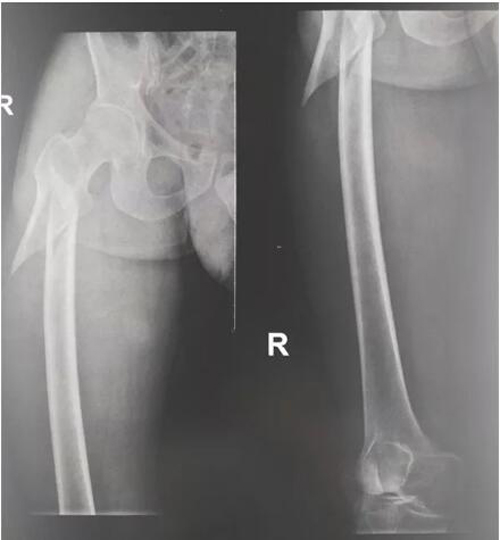

两周前,林老先生在家中整理家务,在爬上人字梯子的时候不慎摔倒,倒地后,右下肢疼痛难忍,余无出血等症状。家属闻声后发现林老先生倒于地上,随后紧急将林老先生送至当地医院,急诊X光检查显示右侧股骨粗隆下骨折,收治入院后,当地医院择期为林老先生行“右侧股骨骨折行切开内固定手术”。骨科手术术程顺利,但林老先生在术后突发不能言语伴反应迟钝,认知下降,对答欠佳,表达下降,躁动不安,肢体无力,经神经内科处理后效果欠佳。为进一步诊治,家属带林老先生来广东三九脑科医院神经内一科住院治疗。

术前X光影像 股骨粗隆下骨折